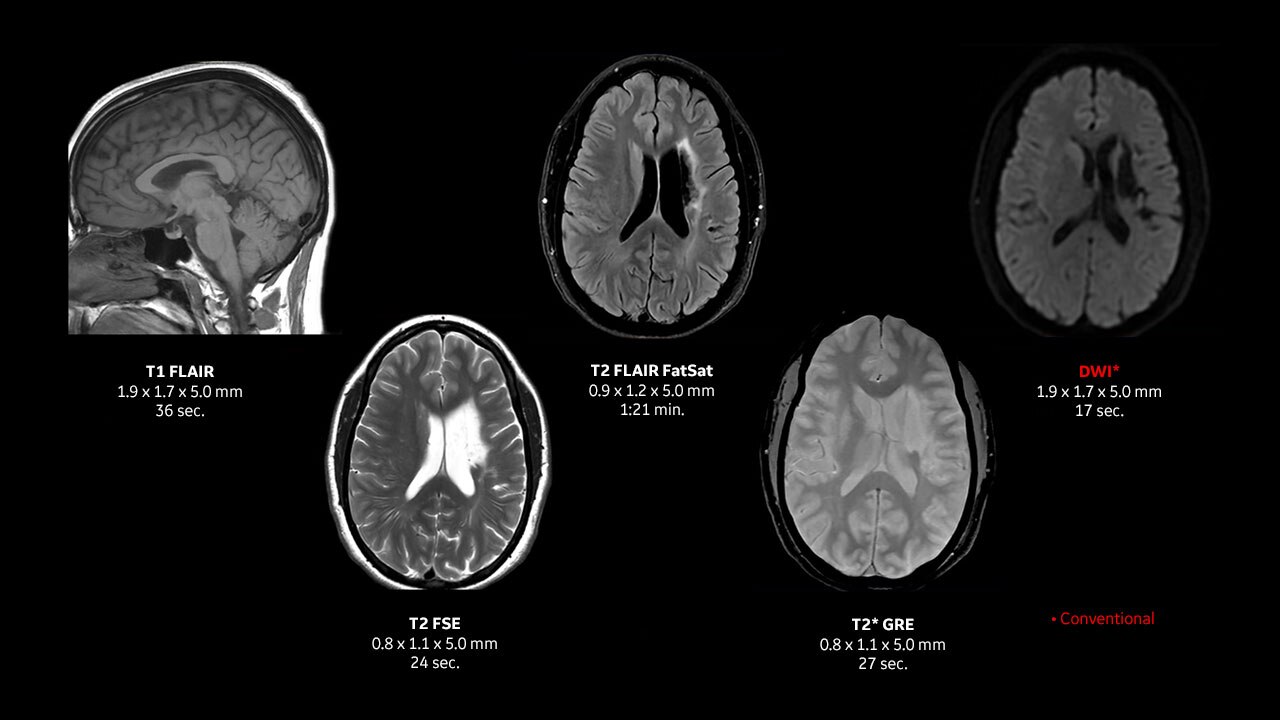

Le immagini incluse in questo documento sono esempi rappresentativi e possono variare in base alle configurazioni.